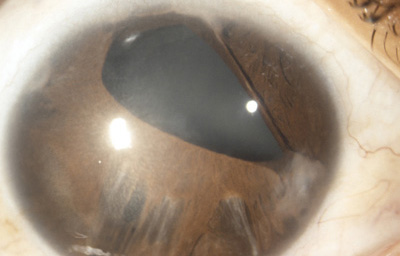

Diastasis: Significa la presencia de agujeros en la raíz del Iris parecidos a una Iridodiálisis

Diastasis del Iris: en un caso de Atrofia Esencial del Iris (Síndrome ICE)

Archivo Fotográfico Dr. Francisco Barraquer